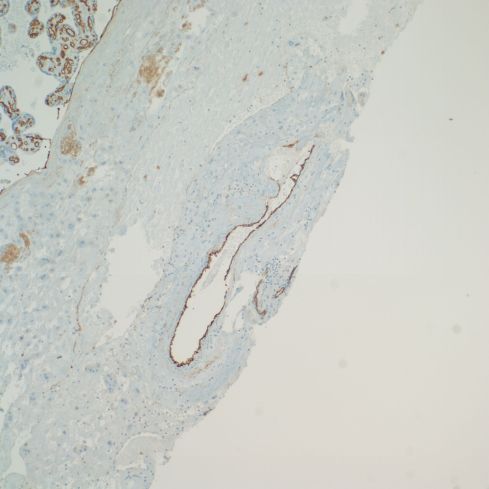

The lining of base of the placenta on the intervillous surface appears to have an endothelial phenotype, as do vessels that are likely veins. The arteries maintain a trophoblast phenotype, but more systematic studies may show less of a dichotomy (Figs 30,31).

Fig 31: This is the same placenta showing brown immunostaining with an antibody to platelet endothelial cell adhesion molecule (CD31) that stains endothelial cells in the fetal vessels in the villi, and the lining of a vessel in the decidua, which may be a large vein, but a deeper portion of a spiral artery cannot be excluded. (CD31, 10x)